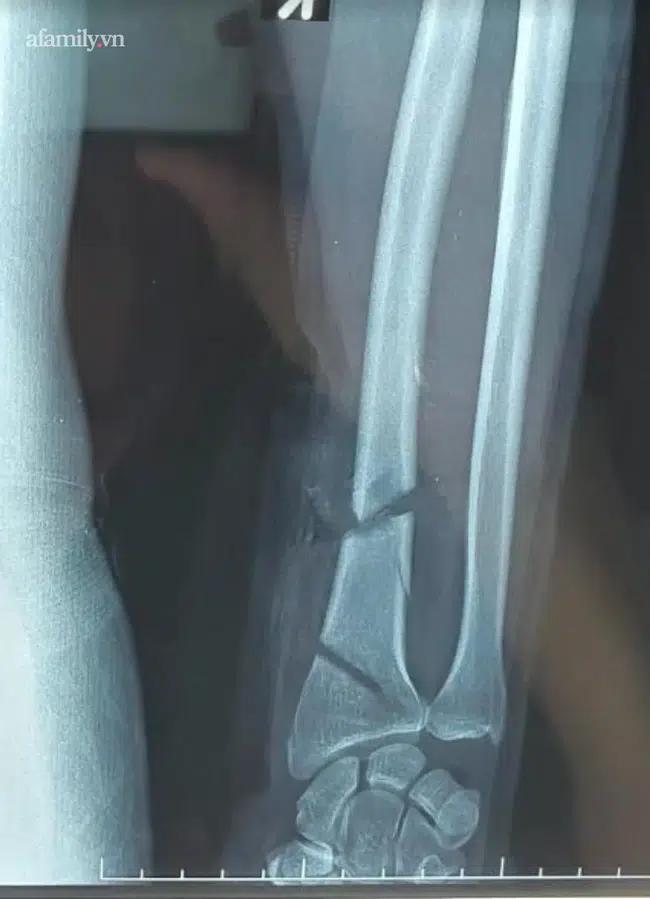

Hình ảnh chụp X-quang của ông V. trước khi phẫu thuật

Theo VTC, vết thương vùng cổ tay phải rất phức tạp, do 2 đường cắt khoảng 2/3 chu vi cổ tay, đứt gần hết mạch máu, gân cơ và thần kinh, xương quay và một số gân cơ, mạch máu vùng cổ tay đứt 2 đoạn. Đồng thời, động mạch quay đứt 2 đoạn, dập nát nên các bác sĩ phải lấy tĩnh mạch ở nơi khác ghép vào.